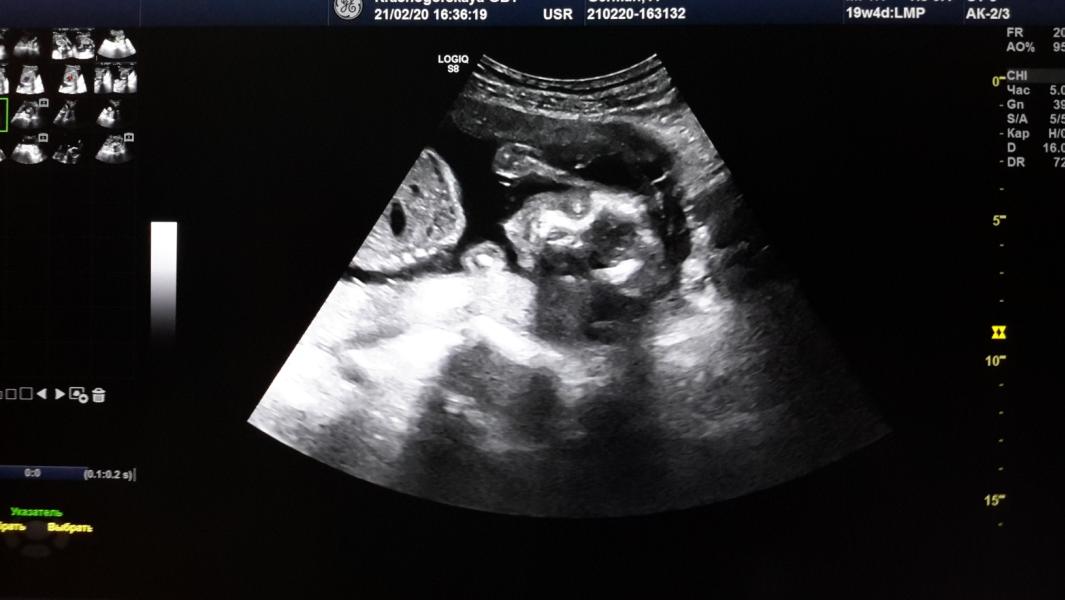

20 недель!!! 20, Карл!!! Как же летит время 🙈🙈🙈.. Малыш 360 г. Маленький пухлый сладыш N2 ❤️